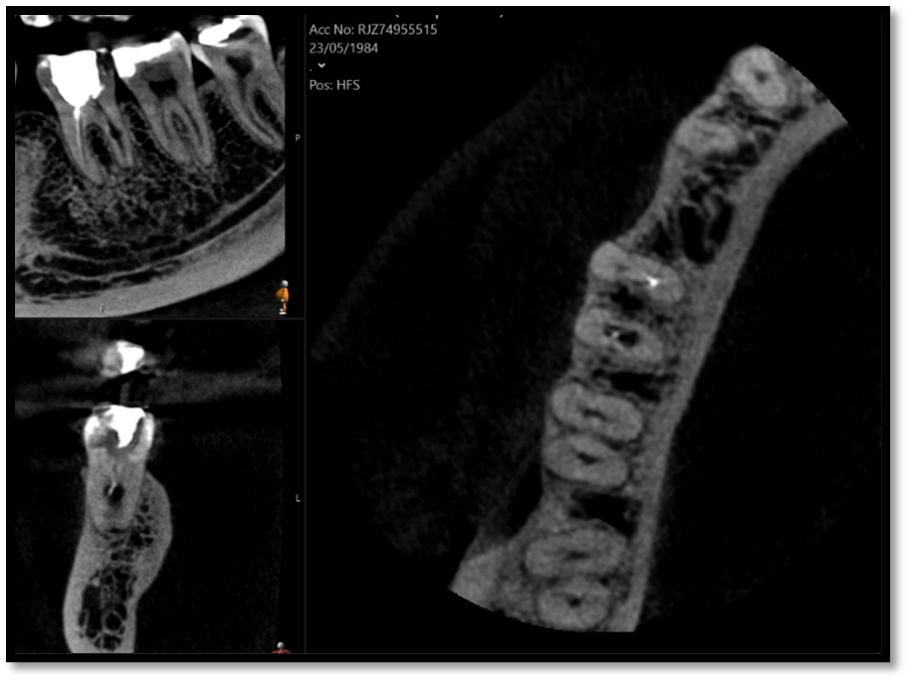

Fractured file removal and re-rct

Pre-op